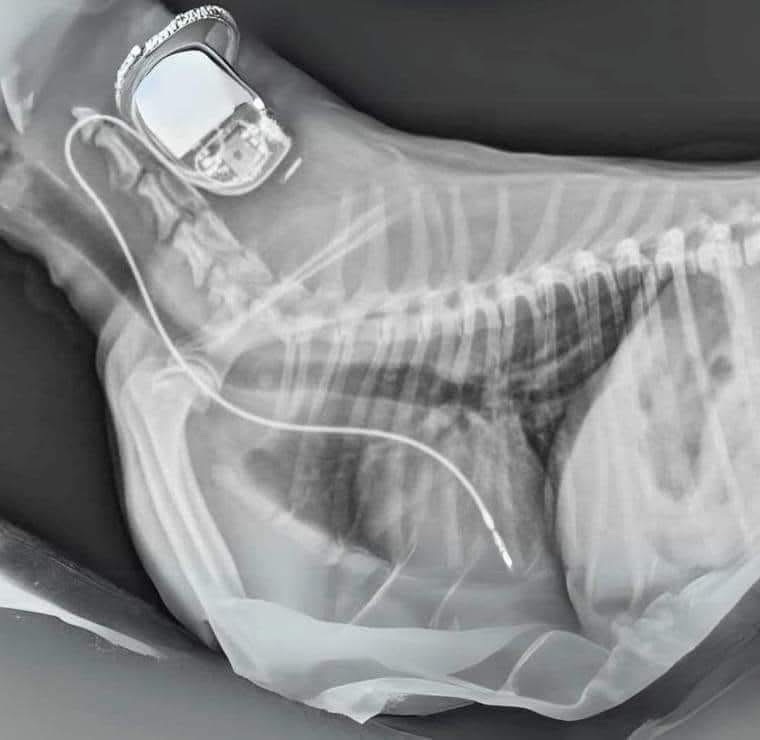

Did you know that if you have a pacemaker, you can include it in your Will to be donated to a dog in need after you pass away?

Although pacemakers cannot be used for another human, they can help dogs with heart problems and potentially save their lives. You can arrange for the pacemker to be sent to a vet of your choice.